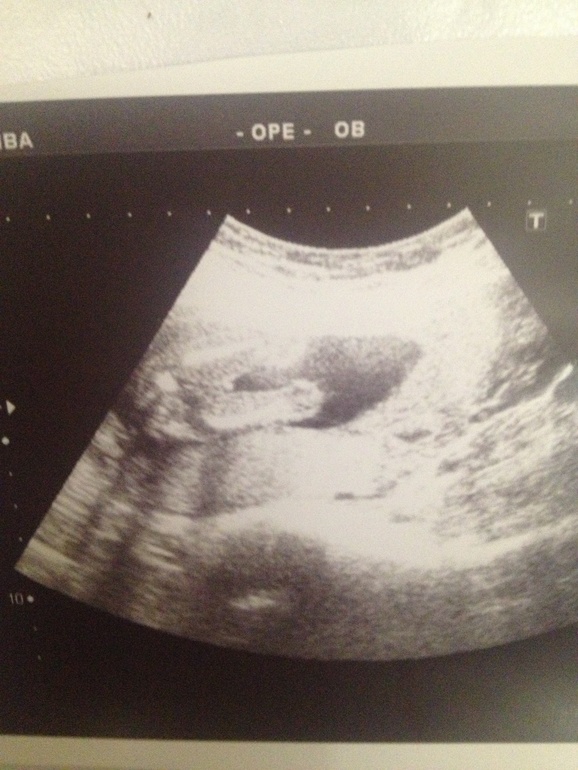

Девочка на узи 16

Девочка на узи 16 112 фотографий